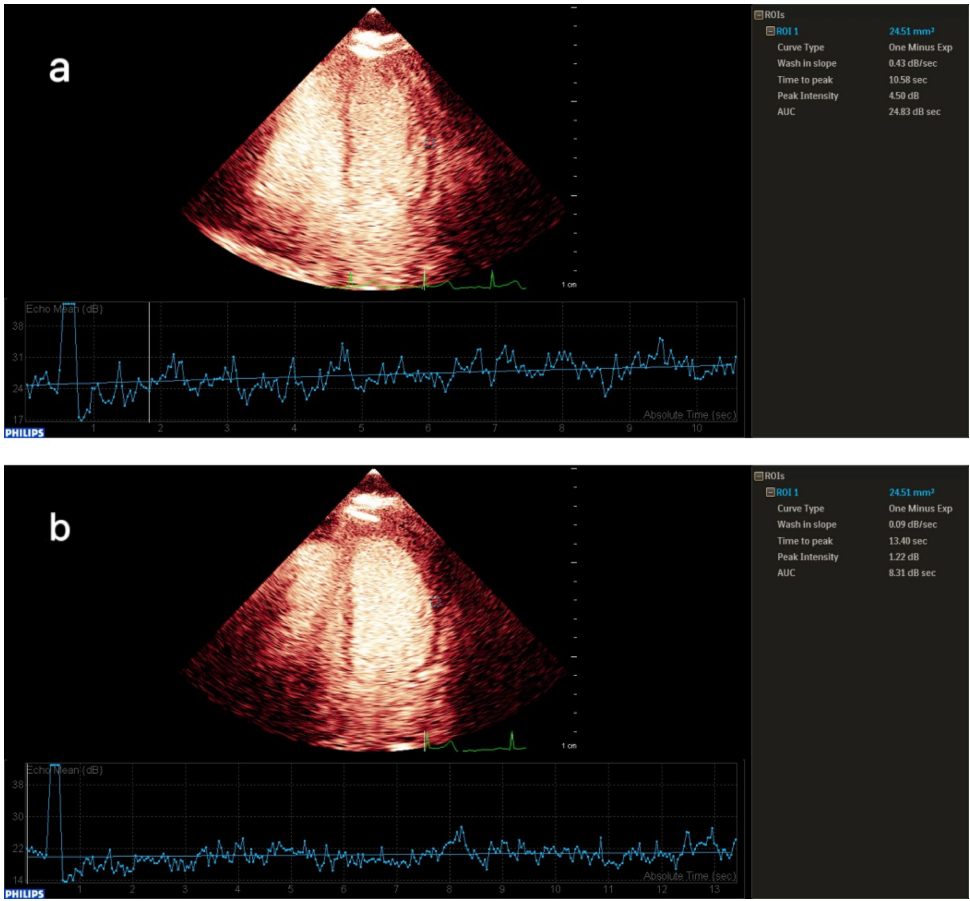

研究团队采用多模态影像评估策略,对2022-2025年间208例胸痛患者进行筛选,最终纳入62例经冠状动脉造影(CAG)或CT血管造影(CCTA)排除阻塞性病变但AS-MCE阳性的INOCA患者。关键技术包括:使用飞利浦EPIQ CVx超声系统进行实时心肌声学造影,通过QLab软件分析静息与负荷状态下的心肌灌注参数(峰值信号强度A值、灌注强度β值、心肌血流量A×β值);借助EchoPAC工作站获取左心室整体纵向应变(GLS)及心肌做功参数(全球做功指数GWI、有效做功GCW、 wasted做功GWW等);采用140μg/(kg·min)腺苷静脉泵注进行药物负荷试验。

突破性发现在"心肌血流灌注参数比较"中展现:INOCA组在静息和负荷状态下的β值(10.77±1.38 vs 9.72±1.82)与CFR(0.46 vs 0.63)均显著低于对照组(P<0.05)。